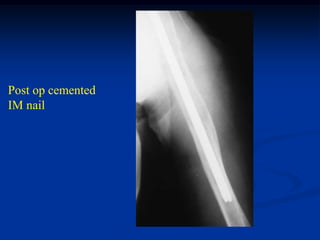

Case #1154            Abdominal Carcinoid to Bone

74 year female with

metastatic abdominal

carcinoid to humerus

Post op cemented

IM nail